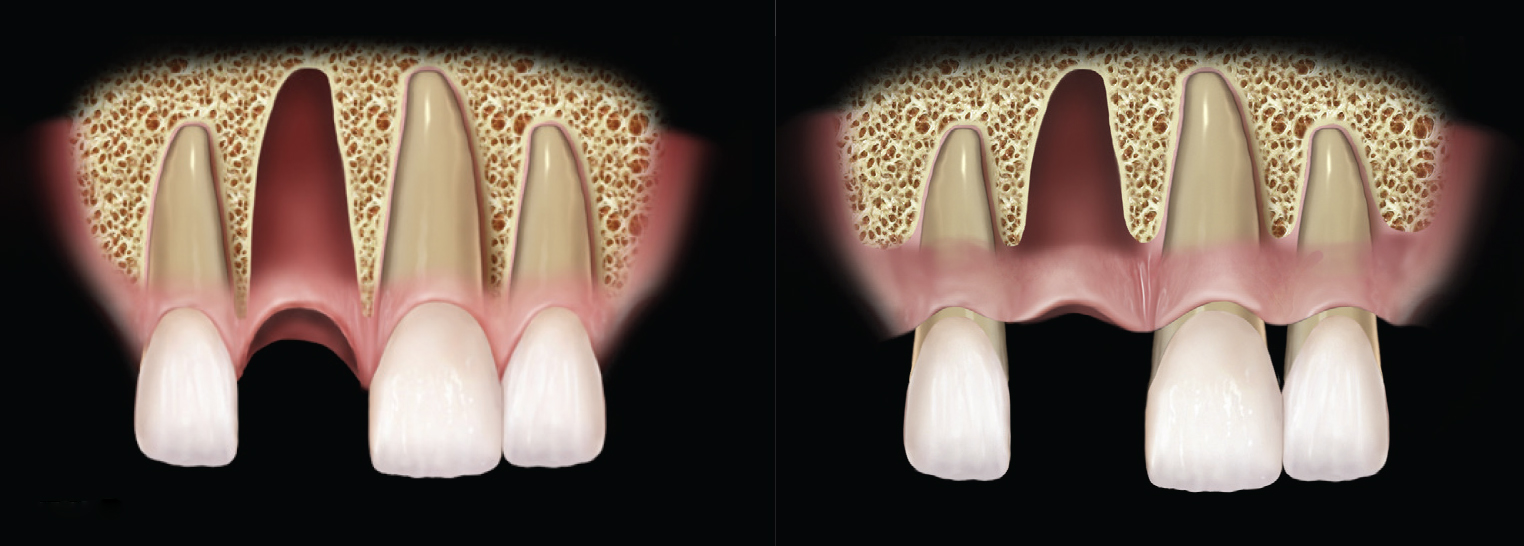

Grade I sockets are the most ideal. Following tooth extraction, a socket that has an intact buccal plate, adequate interproximal bone, and satisfactory apical topography will fall into this category. In this classification, an intact buccal plate is defined as having no fissures or dehiscences and less than 25% loss of height (Figure 4, left; Figure 5, left). This percentage of buccal plate loss was selected as the cutoff based on the average root length of single-rooted teeth, which is 14.2 mm,25 and the amount of buccal plate that can be reliably regenerated during immediate implant placement. Adequate apical topography is defined as enough bone present apical to the extraction site to allow for engagement of 3 mm to 4 mm of a properly positioned immediate dental implant (Figure 2).1,2 Adequate interproximal bone is defined as no or mild (up to 2 mm) periodontal bone loss on the adjacent teeth as to allow for support of the interproximal soft tissue and to enable placement of the platform of an immediate implant in the proper apical-coronal position relative to the adjacent teeth while still being bordered by bony walls on the mesial and distal aspects26 (Figure 3, left).

Grade II sockets are differentiated from Grade I by the amount and quality of the remaining buccal plate. A Grade II socket has a fissure, dehiscence, or deficiency of the buccal plate totaling a 25% to 50% loss. Like Grade I sockets, they have adequate interproximal bone and apical topography (Figure 3, left; Figure 4, center; Figure 5, center).

(Left) Example of adequate interproximal bone. The periodontium is healthy, and the bony peeks on either side of the extraction socket are aiding in supporting the interproximal papilla. (Right) A mildly reduced periodontium. Interproximal bone is present; there is enough bone to support full papilla in the embrasure spaces of the natural dentition.